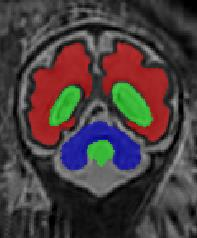

Limiting failures of machine learning systems is of paramount importance for safety-critical applications. In order to improve the robustness of machine learning systems, Distributionally Robust Optimization (DRO) has been proposed as a generalization of Empirical Risk Minimization (ERM). However, its use in deep learning has been severely restricted due to the relative inefficiency of the optimizers available for DRO in comparison to the wide-spread variants of Stochastic Gradient Descent (SGD) optimizers for ERM. We propose SGD with hardness weighted sampling, a principled and efficient optimization method for DRO in machine learning that is particularly suited in the context of deep learning. Similar to a hard example mining strategy in practice, the proposed algorithm is straightforward to implement and computationally as efficient as SGD-based optimizers used for deep learning, requiring minimal overhead computation. In contrast to typical ad hoc hard mining approaches, we prove the convergence of our DRO algorithm for over-parameterized deep learning networks with ReLU activation and a finite number of layers and parameters. Our experiments on fetal brain 3D MRI segmentation and brain tumor segmentation in MRI demonstrate the feasibility and the usefulness of our approach. Using our hardness weighted sampling for training a state-of-the-art deep learning pipeline leads to improved robustness to anatomical variabilities in automatic fetal brain 3D MRI segmentation using deep learning and to improved robustness to the image protocol variations in brain tumor segmentation. Our code is available at https://github.com/LucasFidon/HardnessWeightedSampler.